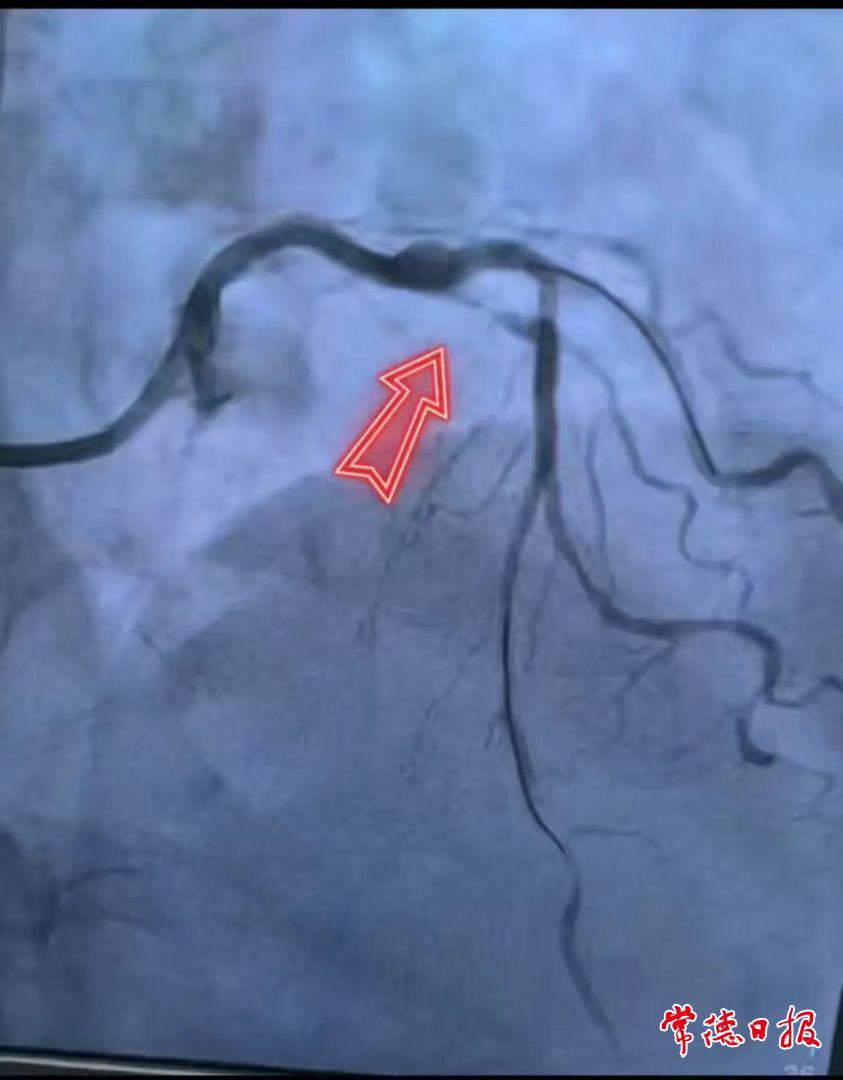

患者于奶奶长期受胸骨后疼痛困扰,外院胃镜诊断为慢性萎缩性胃炎,抑酸治疗后“烧心感”虽缓解,胸痛却依然折磨着她。近日,于奶奶在家人的陪伴下来到了常德市第一中医医院心血管科就诊。经详细了解病情、全面检查后,接诊的龙俊杰副主任医师判断此为高危胸痛,随后为其进行冠状动脉造影检查,结果提示:冠状动脉多处严重狭窄并钙化病变。

因患者高龄体弱无法耐受开胸搭桥手术,心血管科二病区负责人周怀能主任团队决定采用介入方案——先以血管内超声(IVUS)精准评估狭窄程度,再用冠状动脉旋磨术将阻塞冠脉内钙化的斑块磨开,随后在前降支中段植入支架。手术历时2小时,彻底疏通了“堵塞的生命通道”,患者术后恢复良好,目前已康复出院。